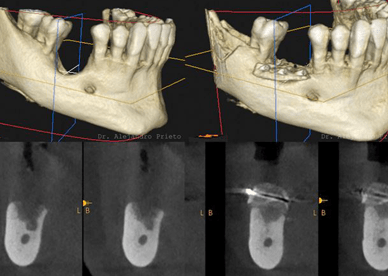

Consultation and planning: We begin with a complete examination of your mouth. Digital X-rays or 3D scans show us the shape and thickness of your jawbone. This planning allows us to choose the ideal position and size for your screw.

Screw Placement: We carefully insert the screw into the hole, using precise measurements to achieve the correct depth. Our clinic uses advanced digital guides and torque controls to ensure the screw is perfectly straight and properly secured. In many cases, we place a healing cap or immediate abutment before closing.

We take care of every step in our own clinic: 3D digital planning, precision surgical guides, and crown fabrication in our state-of-the-art laboratory. This allows us complete control over fit and aesthetics. Our team of expert doctors, led by Dr. Alejandro Prieto, has years of experience in dental implantology. Plus, we stand behind our implants: many of our treatments include long-term warranties for your peace of mind.